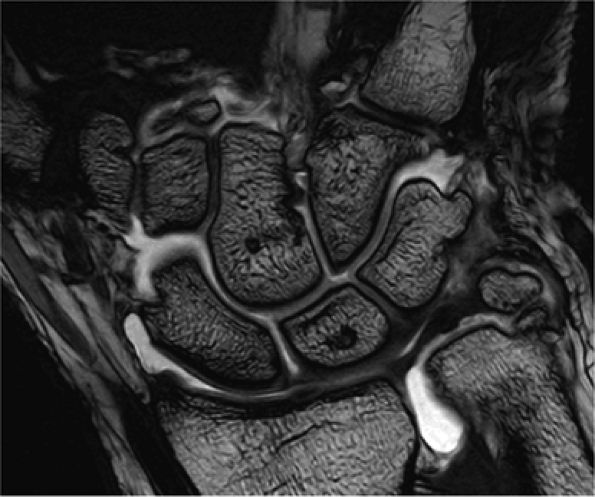

FIGURE 1.2 ● High-resolution wrist arthrography. 3D-FIESTA sequence (steady state free precession), TR 9.2 msec, TE 3.1 msec, voxel size 0.26 × 0.28 × 1.2 mm, acquisition time 3 minutes, 28 seconds.